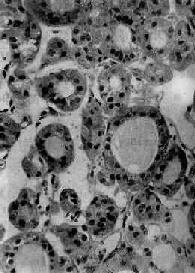

1.滤泡性腺瘤(follicular adenoma)根据滤泡分化程度,又可分为以下几种亚型:①胚胎性腺瘤(embryonal adenoma),瘤细胞小,排列成条索状或小片状,有少量不完整的滤泡状腺腔散在,有较多呈水肿的疏松纤维间质;②胎儿型腺瘤(fetal adenoma),由许多小滤泡构成,上皮细胞为小立方形,滤泡腔内多不含胶质,与胎儿甲状腺组织相似(图15-9)。间质较丰富,呈水肿或粘液变性,此型易发生囊性变或出血;③单纯型腺瘤(simple adenoma),由与正常甲状腺相似的滤泡构成,间质较少;④胶样腺瘤(colloid adenoma),滤泡较大,充满胶质,间质少;⑤嗜酸性细胞腺瘤(acidophilic cell adenoma,亦称Hürthle cell adenoma),瘤细胞大而多角形,核小,胞浆丰富,有嗜酸性颗粒,排列成索状或巢状,也可形成不完整的滤泡腔。本瘤较少见。

图15-9 胎儿型甲状腺腺瘤